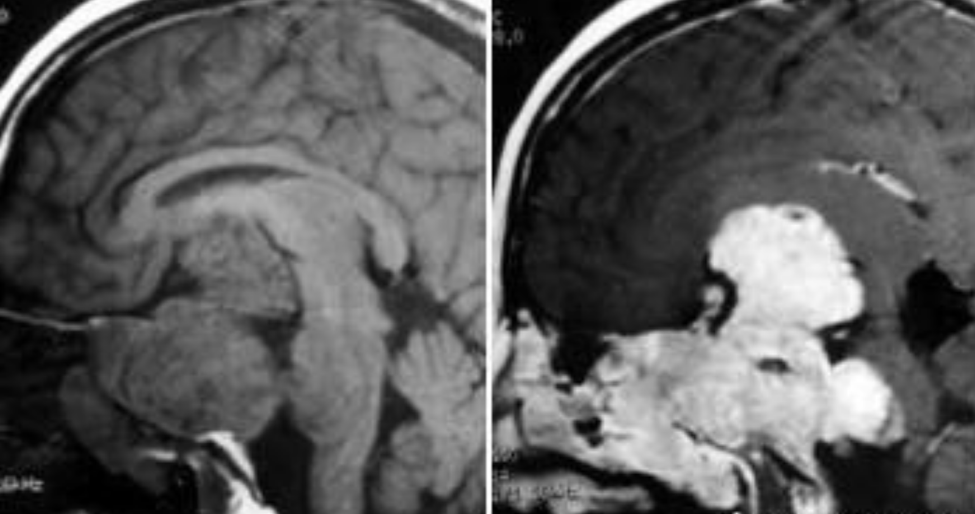

患者40+岁,女性,患者临床症状明显,近1年多来相继头痛、复视、肢体无力、吞咽困难等,当地医院诊断为较大斜坡脑膜瘤,辗转多地医院均告知肿瘤无法全切,术后并发症风险发生率高,后慕名咨询德国国际神经科学中心INI寻求巴特朗菲手术治疗,肿瘤切除97%以上,无相关手术并发症。

术前MR示:斜坡较大脑膜瘤,压迫脑干、颅神经,侵犯基底动脉等

术后MR显示:肿瘤近全切除,术后未见脑血肿、脑水肿,神经血管、脑干等组织保护完好。